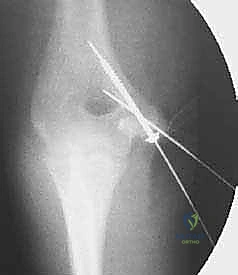

Reduction and Provisional Fixation

The avulsed fragment, tethered by the flexor-pronator mass and UCL, is mobilized and anatomically reduced onto its footprint on the distal humerus. Reduction is often facilitated by flexing the elbow and pronating the forearm to relax the flexor-pronator tension. Once reduced, the fragment is provisionally stabilized using one or two smooth Kirschner wires (K-wires), typically 0.045 or 0.062 inches in diameter.

1. Cannulated Screws: For most adolescents and adults with a sufficiently large fragment, fixation with one or two partially threaded cannulated screws (typically 3.5 mm or 4.0 mm) is the gold standard. A guidewire is advanced through the center of the fragment, directed anteriorly and laterally towards the lateral cortex of the distal humerus, carefully avoiding penetration into the olecranon or coronoid fossae. The screw length is measured, and the screw is inserted to achieve interfragmentary compression. In skeletally immature patients, care must be taken not to over-compress and crush the physis.

- K-wire Fixation: In very young children with small, predominantly cartilaginous fragments, or in cases of severe comminution, definitive fixation with divergent K-wires may be preferred. The pins are typically bent and cut outside the skin for later removal in the clinic, or buried subcutaneously.

Following definitive fixation, orthogonal fluoroscopic imaging is obtained to confirm anatomical reduction, appropriate hardware length, and absence of intra-articular penetration.